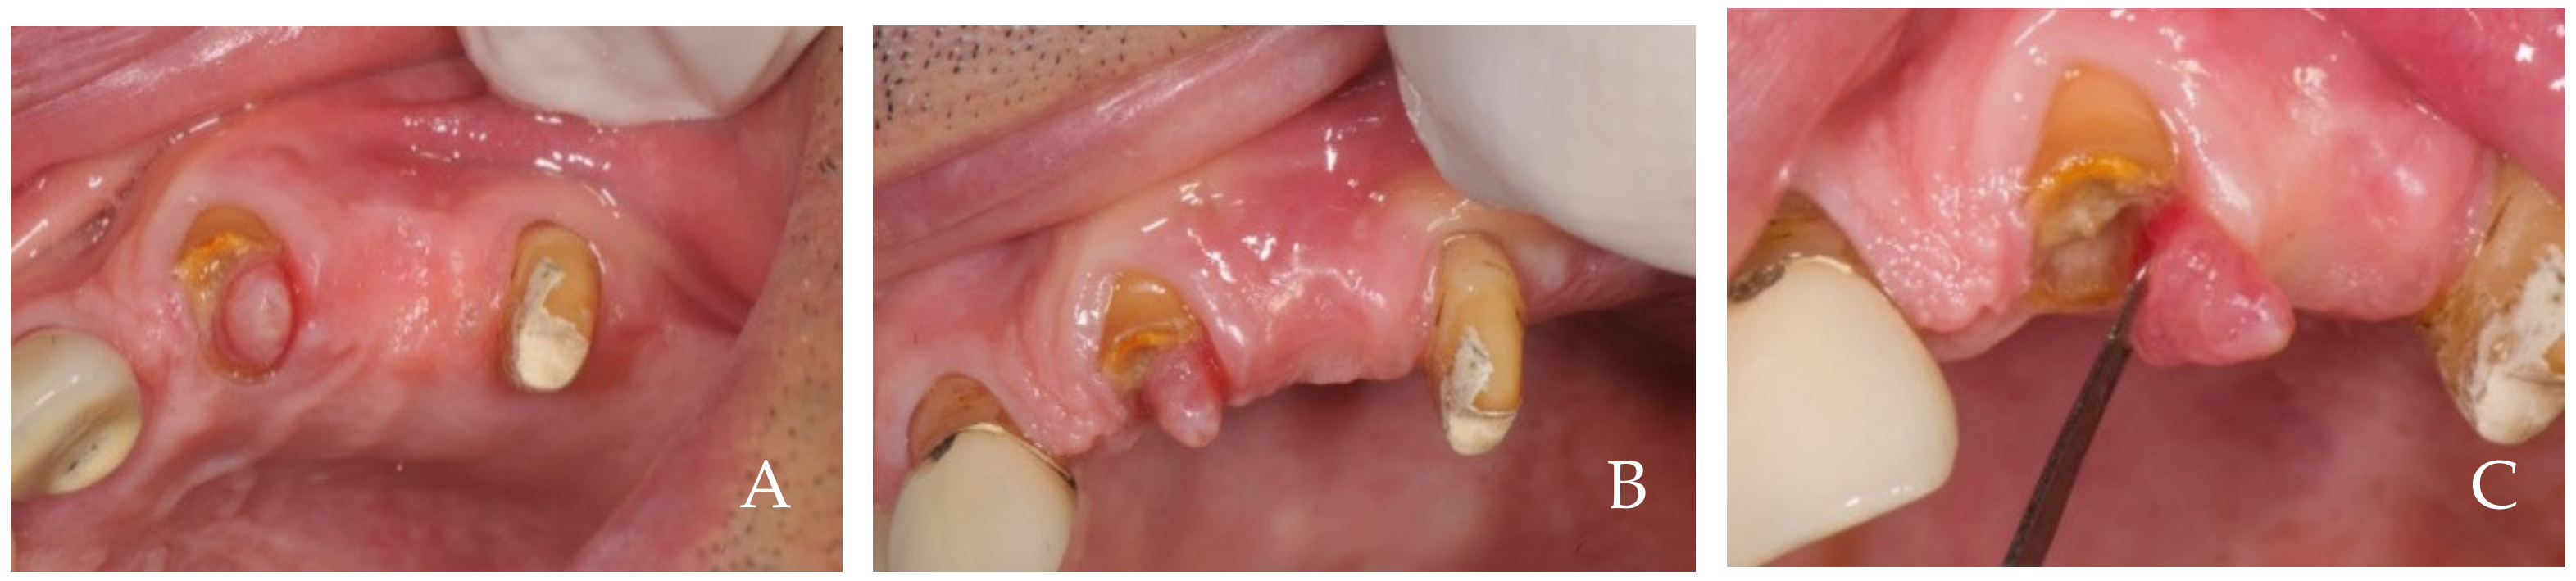

2. Clinical Examples of Oral Soft Tissue Growth